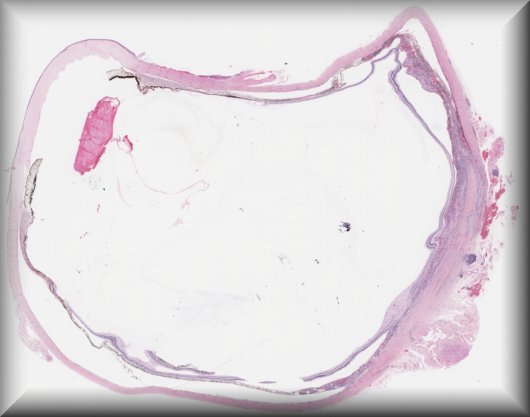

Julia Weller (Erlangen, Germany): Diffuse choroidal hemangioma, intraocular ossification, secondary angle closure glaucoma in a young female patient with Sturge-Weber syndrome. |